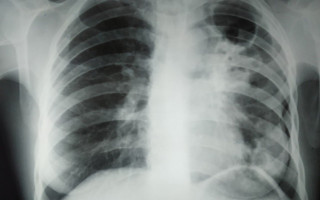

В Україні з’являються випадки позалегеневого туберкульозу – у ЦГЗ відповіли, чи існує сплеск захворюваності

У ЦГЗ повідомляють про стрімке зростання антибіотикорезистентності та додаткові ризики для громадського здоров’я через війну, але зростання захворюваності не фіксують.